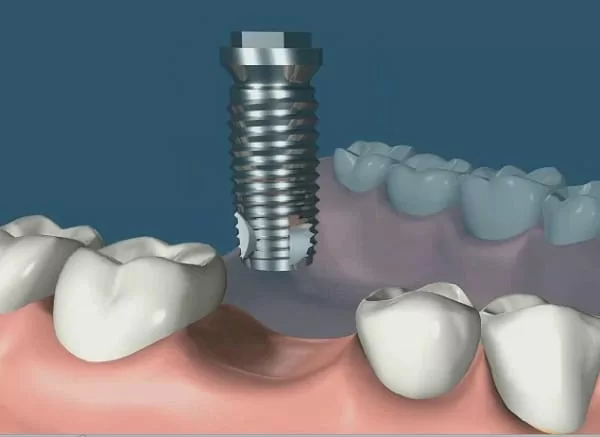

植牙成功關鍵,要美觀更要兼顧穩定性!!

謝醫師說 : 這顆牙齒拔掉後,建議先充填骨粉及再生膜,施行牙嵴保存術,保留牙嵴的寬度及高度,以便將來有好的骨質條件進行植牙。

所以等約四個月後植牙,再等待三個月以新科技的植牙穩定度測量儀測量骨整合程度,發現骨整合情況良好,隨即以"臨時牙套"進行牙齦塑型,再製作全瓷冠恢復我的咀嚼功能。